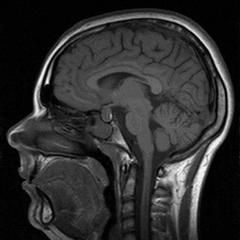

С помощью метода магнитной томографии можно получить изображение любых внутренних сред организма, причем изображение послойное и очень точное, что позволяет достоверно определять не только размеры, но и местоположение, скажем, опухоли или кисты, и ее взаимодействие с соседними органами. Благодаря этому магнитная томография широко используется в нейрологии, с ее помощью диагностируют большинство заболеваний головного и спинного мозга.

Вообще стоит сказать, что метод магнитного резонанса настолько информативен и безопасен, что его можно применять практически во всех случаях диагностики болезней внутренних органов. Пожалуй, единственное, что препятствует его еще более широкому, чем в настоящее время, использованию, это довольно высокая стоимость исследования, поскольку весьма дорогой является аппаратура для его проведения. Тем не менее, сейчас вопрос «где сделать хорошее МРТ?» обычно уже не стоит, поскольку каждое крупное медицинское учреждение располагает такой возможностью.